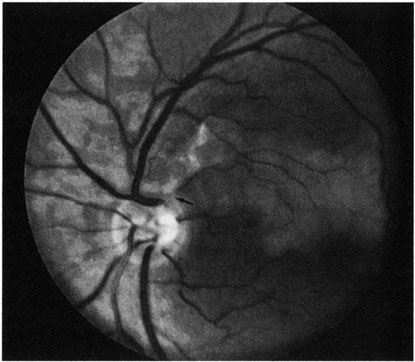

Fig. 1. A: Acute central retinal artery obstruction with a cherry-red spot. B and C: Intravenous fluorescein angiography. There is a delay of dye appearance in the central retinal artery, and when it does appear, it does not fill the arteries completely. D: Ocular coherence tomography (OCT) at the time of occlusion showing the increase in retinal thickness and reflectivity of the inner layers of the retina. E: Seven months later there is significant optic atrophy(G), and the OCT (F) shown now has marked thinning of the retina.

With time, the retinal opacity diminishes, generally leaving an optic nerve that is atrophic (Fig. 1). Frequently, thinned retinal arteries and veins also remain.7,8 No foveolar light reflex is evident, and a finely pigmented appearance of the macula is typical.7 In some cases, arterial collaterals develop at the optic disc.9–11 Rarely, anatomoses that exist between the central retinal artery and the ciliary arteries become visible as preretinal loops (Nettleship collaterals) after an occlusion at the edge of the disc.12,13,378In approximately 20% of patients, an embolus is evident somewhere in the arterial system.14 Emboli are discussed later.